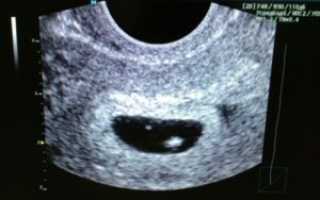

В этом видео показано УЗИ пустого плодного яйца:

Определить пустое плодное яйцо можно только с помощью ультразвукового исследования. Однако всем подряд женщинам не рекомендуется делать УЗИ на ранних сроках, такое обследование нужно проводить только по показаниям, например, при наличии кровянистых выделений или сильных болей в животе.

УЗИ, проведённое слишком рано, может дать ошибочный результат и внести в жизнь беременной ненужный стресс. Нередки случаи, когда диагноз «анэмбриония» оказывается ложным. Очень рано провели УЗИ или срок беременности оказался меньше, чем предполагается, и маленький эмбрион просто не увидели.

Определить анэмбрионию по УЗИ можно не ранее 5-6 недель беременности, но и на этом сроке могут быть ошибки.

При подозрении на анэмбрионию нельзя спешить с прерыванием беременности. Во-первых, диагноз может оказаться ложным. Обязательно нужно провести ещё одно ультразвуковое исследование примерно через 7-10 дней.